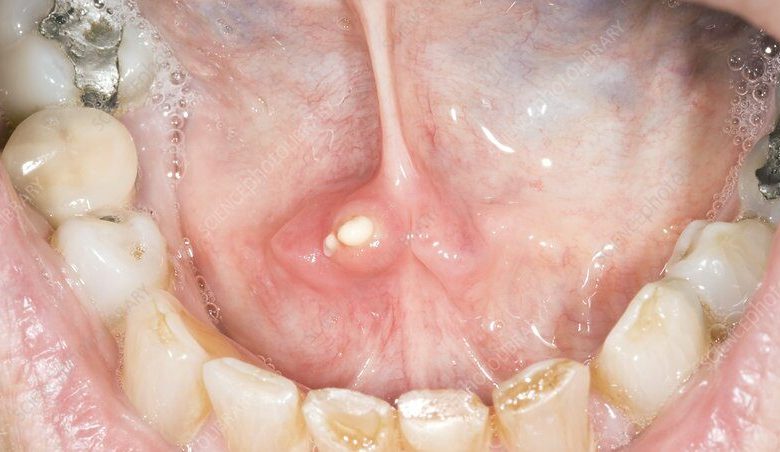

- قد تكون هذه الحصوات، التي يطلق عليها طبيا sialoliths، صلبة، صفراء أو بنية اللون، خشنة بعض الشيء، وفي حجم حبة البازلاء.

- توجد هذه الغدد والقنوات بالقرب من أسنانك العلوية وتحت لسانك وعلى أرضية فمك (أسفل الفك).

- في بعض الحالات، يمكن أن تستقر حصوات اللعاب في القنوات اللعابية، مما يمنع تدفق اللعاب، وهذا يمكن أن يؤدي إلى التهابات، وفي حالات نادرة، كتل مؤلمة من القيح تسمى الخراجات.